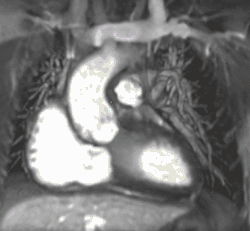

Cardiac magnetic resonance imaging (cardiac MRI, CMR), also known as cardiovascular MRI, is a magnetic resonance imaging (MRI) technology used for non-invasive assessment of the function and structure of the cardiovascular system.[2] Conditions in which it is performed include congenital heart disease, cardiomyopathies and valvular heart disease, diseases of the aorta such as dissection, aneurysm and coarctation, coronary heart disease. It can also be used to look at pulmonary veins.[3]